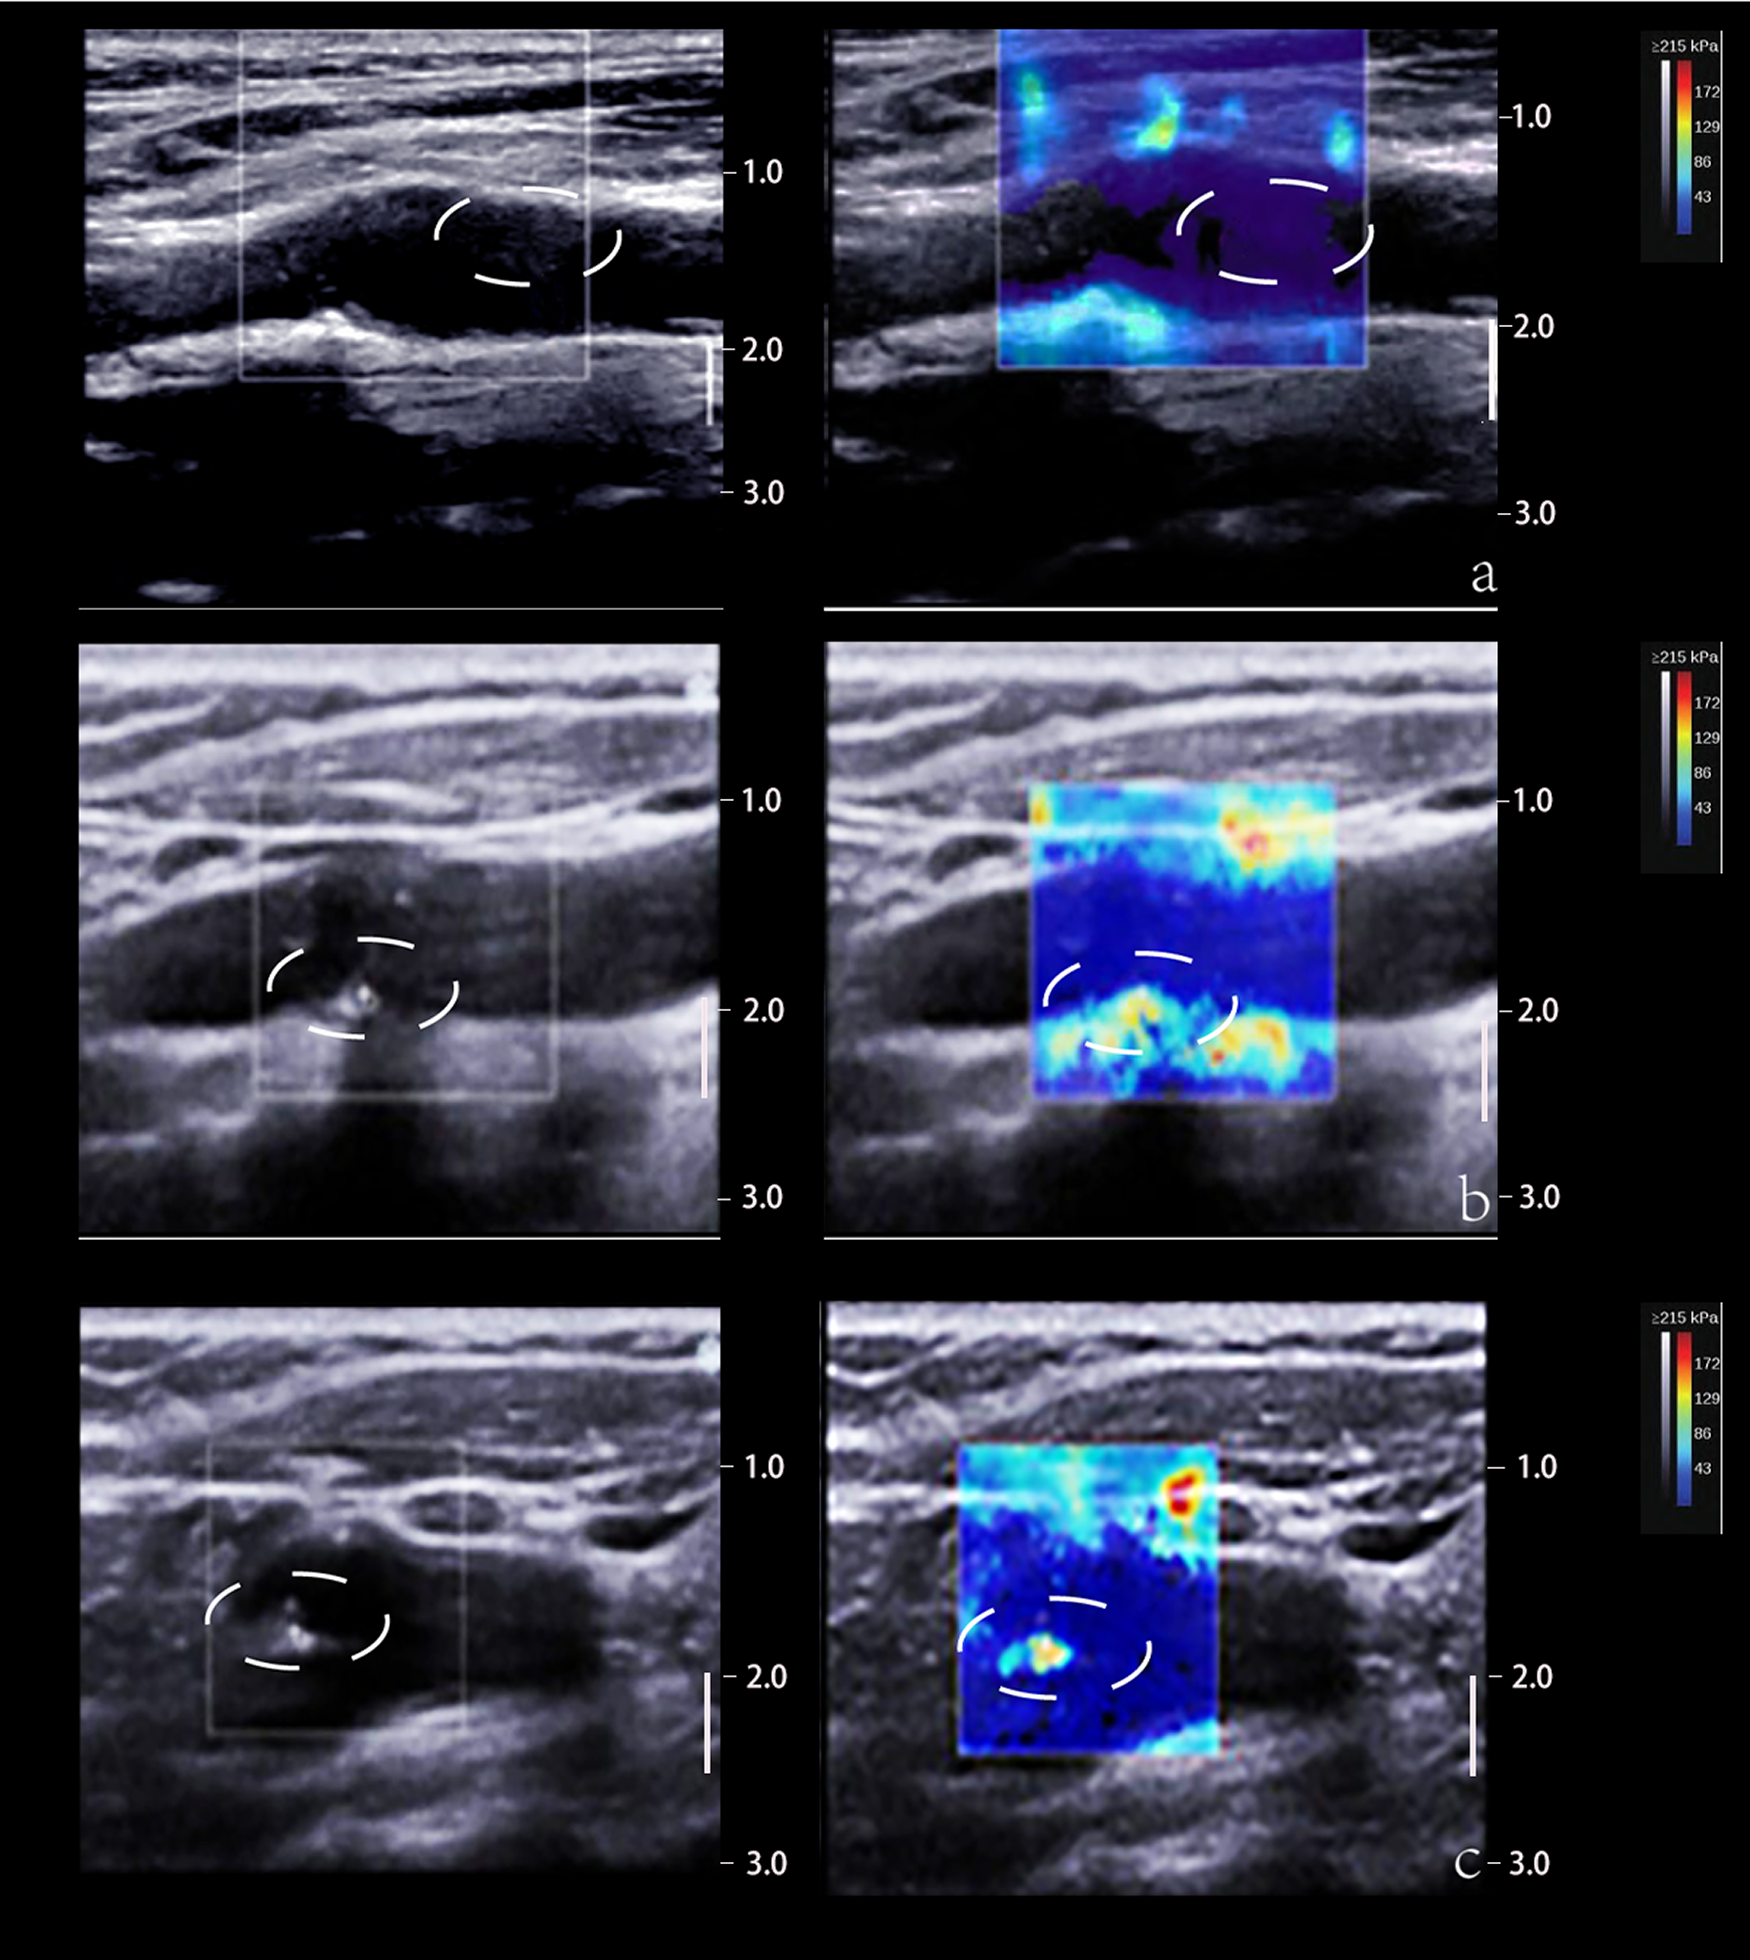

SWE estimates tissue elasticity by tracking the transverse velocity of the tissue after it has been subjected to an external force. The transducer emits a transverse wave through an acoustic radiation force pulse (ARFI) and measures the speed of the transverse wave propagation through the tissue, expressed as Young's modulus (YM), which reflects the tissue's resistance to elastic deformation and is largely depended on the composition of the tissue. Soft tissues such as lipid cores in plaques tend to show obvious elastic deformation, lower YM and lower transverse wave velocity; whereas harder tissues and lesions show less elastic deformation (77, 84) (Figure 4).

Figure 4

2D and SWE imaging of plaques with different hardness. (Panel A) The 2D image displays a predominantly hypoechoic plaque and the SWE image displays a blue color at the plaque, suggesting a soft texture. (Panel B) The 2D image shows a predominantly mixed echogenicity of the plaque and the SWE image shows a red-blue mix at the plaque, suggesting that the texture of the plaque is between soft and hard. (Panel C) The 2D image demonstrates that the plaque is predominantly strong echogenic and the SWE image demonstrates a red color at the plaque, suggesting a hard texture. The white dotted lines depict the plaque area.